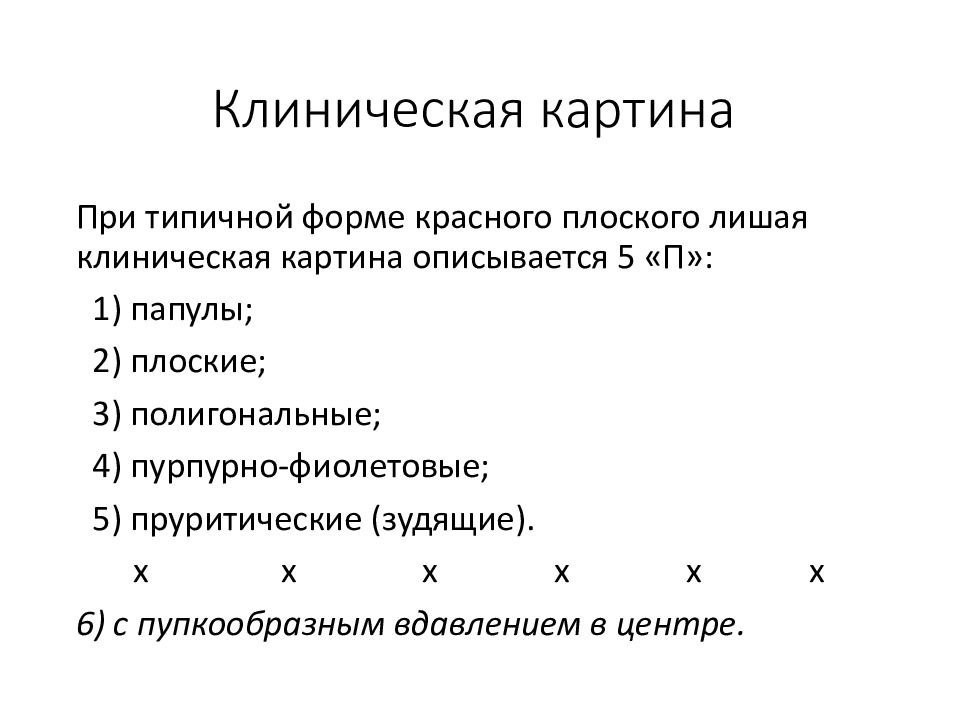

Фото Красного Плоского

Фото Красного Плоского 103 фото